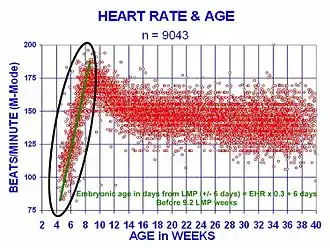

The human heart beats more than 2.8 billion times in an average lifetime.[65] The heartbeat of a human embryo begins at approximately 21 days after conception, or five weeks after the last normal menstrual period (LMP), which is the date normally used to date pregnancy in the medical community. The electrical depolarizations that trigger cardiac myocytes to contract arise spontaneously within the myocyte itself. The heartbeat is initiated in the pacemaker regions and spreads to the rest of the heart through a conduction pathway. Pacemaker cells develop in the primitive atrium and the sinus venosus to form the sinoatrial node and the atrioventricular node respectively. Conductive cells develop the bundle of His and carry the depolarization into the lower heart.

The human heart begins beating at a rate near the mother's, about 75–80 beats per minute (bpm). The embryonic heart rate then accelerates linearly for the first month of beating, peaking at 165–185 bpm during the early 7th week, (early 9th week after the LMP). This acceleration is approximately 3.3 bpm per day, or about 10 bpm every three days, an increase of 100 bpm in the first month.[66]

After peaking at about 9.2 weeks after the LMP, it decelerates to about 150 bpm (+/-25 bpm) during the 15th week after the LMP. After the 15th week the deceleration slows reaching an average rate of about 145 (+/-25 bpm) bpm at term. The regression formula which describes this acceleration before the embryo reaches 25 mm in crown-rump length or 9.2 LMP weeks is: